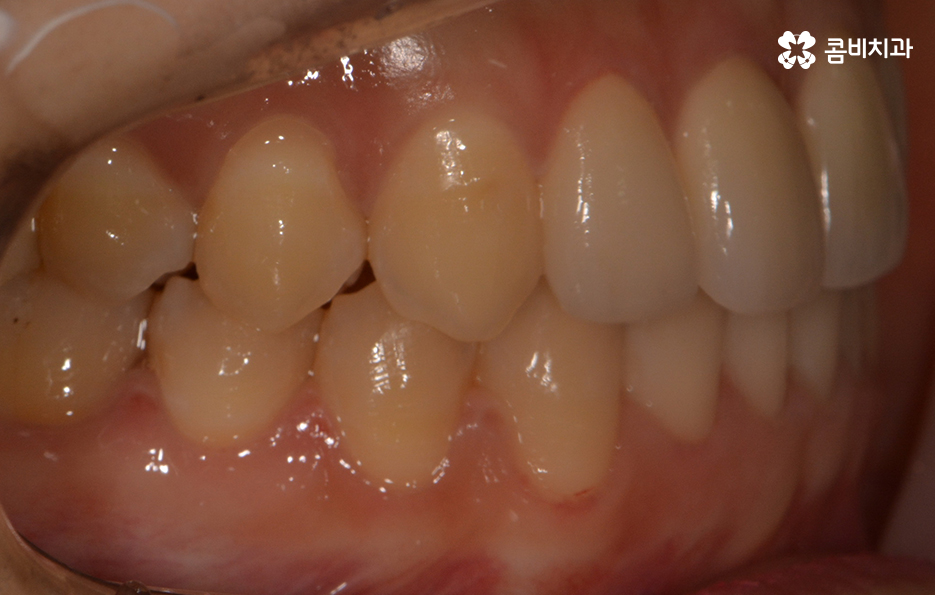

옆모습을 볼 때 치아 사이가 유독 벌어져 보이는데 심미적으로도

부담감을 느끼실 수 있지만 음식물이 치아 사이에 낀다거나

치아의 벌어짐으로 인해 치열이 반듯하게 자라지 못하기도 합니다.

전체적인 치열 상태가 비교적 가지런한 편이었기 때문에

약 1년 정도 클리피씨교정을 통해서 치열과 교합 개선이 진행 되었습니다.